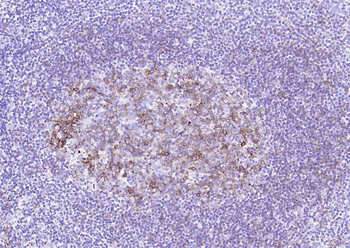

| Tested applications | IHC |

| Dilution range | Immunohistochemistry (Frozen & Formalin-fixed) (1-2ug/ml for 30 minutes at RT),(Staining of formalin-fixed tissues is enhanced by boiling tissue sections in 10mM Citrate Buffer, pH 6.0, for 10-20 min followed by cooling at RT for 20 minutes),Optimal dilution for a specific application should be determined. |

| Application notes | Positive Control: Human tonsil or lymph node |